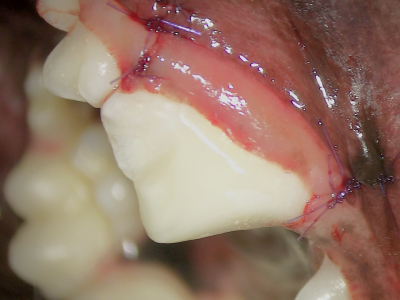

歯肉を戻し縫合しました。